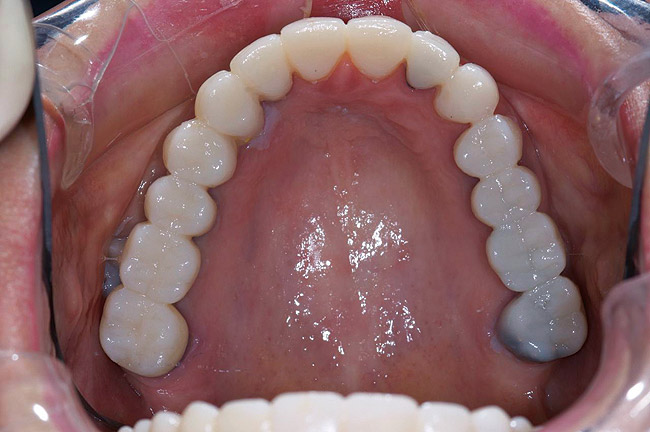

Figure 30  Final restorations.

Figure 30

Figure 31  Technical precision and artistic skill blend into a pleasing smile and a happy patient.

Figure 31